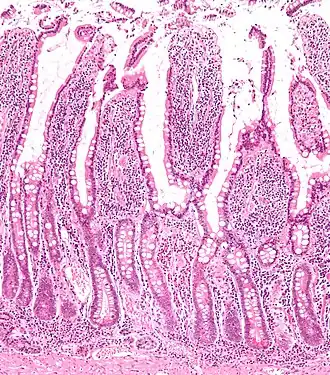

Микропрепарат стенки тонкой кишки

Стенка тонкой кишки образована слизистой оболочкой, подслизистой основой, мышечной и серозной оболочками.

Слизистая оболочка тонкой кишки характеризуется характерным рельефом, образуемым наличием целого ряда анатомических образований: циркулярных складок, ворсинок и кишечных желез или крипт. Благодаря этим структурам увеличивается общая, в том числе и всасывающая поверхность, что способствует выполнению основных биологических функций тонким отделом кишечника[4]:

• циркулярные складки (лат. plicae circulares) сформированы слизистой оболочкой и подслизистой основой тонкой кишки;

• кишечные ворсинки (лат. villi intestinales) образованы выпячиваниями слизистой оболочки пальцевидной либо листовидной формы, свободно выступающие в просвет тонкой кишки. Число ворсинок в тонкой кишке весьма значительно: наибольшее их количество в двенадцатиперстной и тощей кишках — насчитывается от 22 до 40 ворсинок на один квадратный миллиметр слизистой оболочки. Несколько меньше их в подвздошной кишке — от 18 до 31 ворсинки на один квадратный миллиметр;

• кишечные железы или крипты (лат. glandulae seu cryptae intestinales) представлены трубчатыми углублениями, расположенными в собственной пластинке слизистой оболочки, а их устья открываются в просвет тонкой кишки между кишечными ворсинками. При этом на один квадратный миллиметр поверхности слизистой оболочки тонкой кишки приходится до 100 крипт, общее их количество превышает 150 миллионов кишечных желёз на всём протяжении, а общая площадь крипт в тонкой кишке достигает 14 м2.